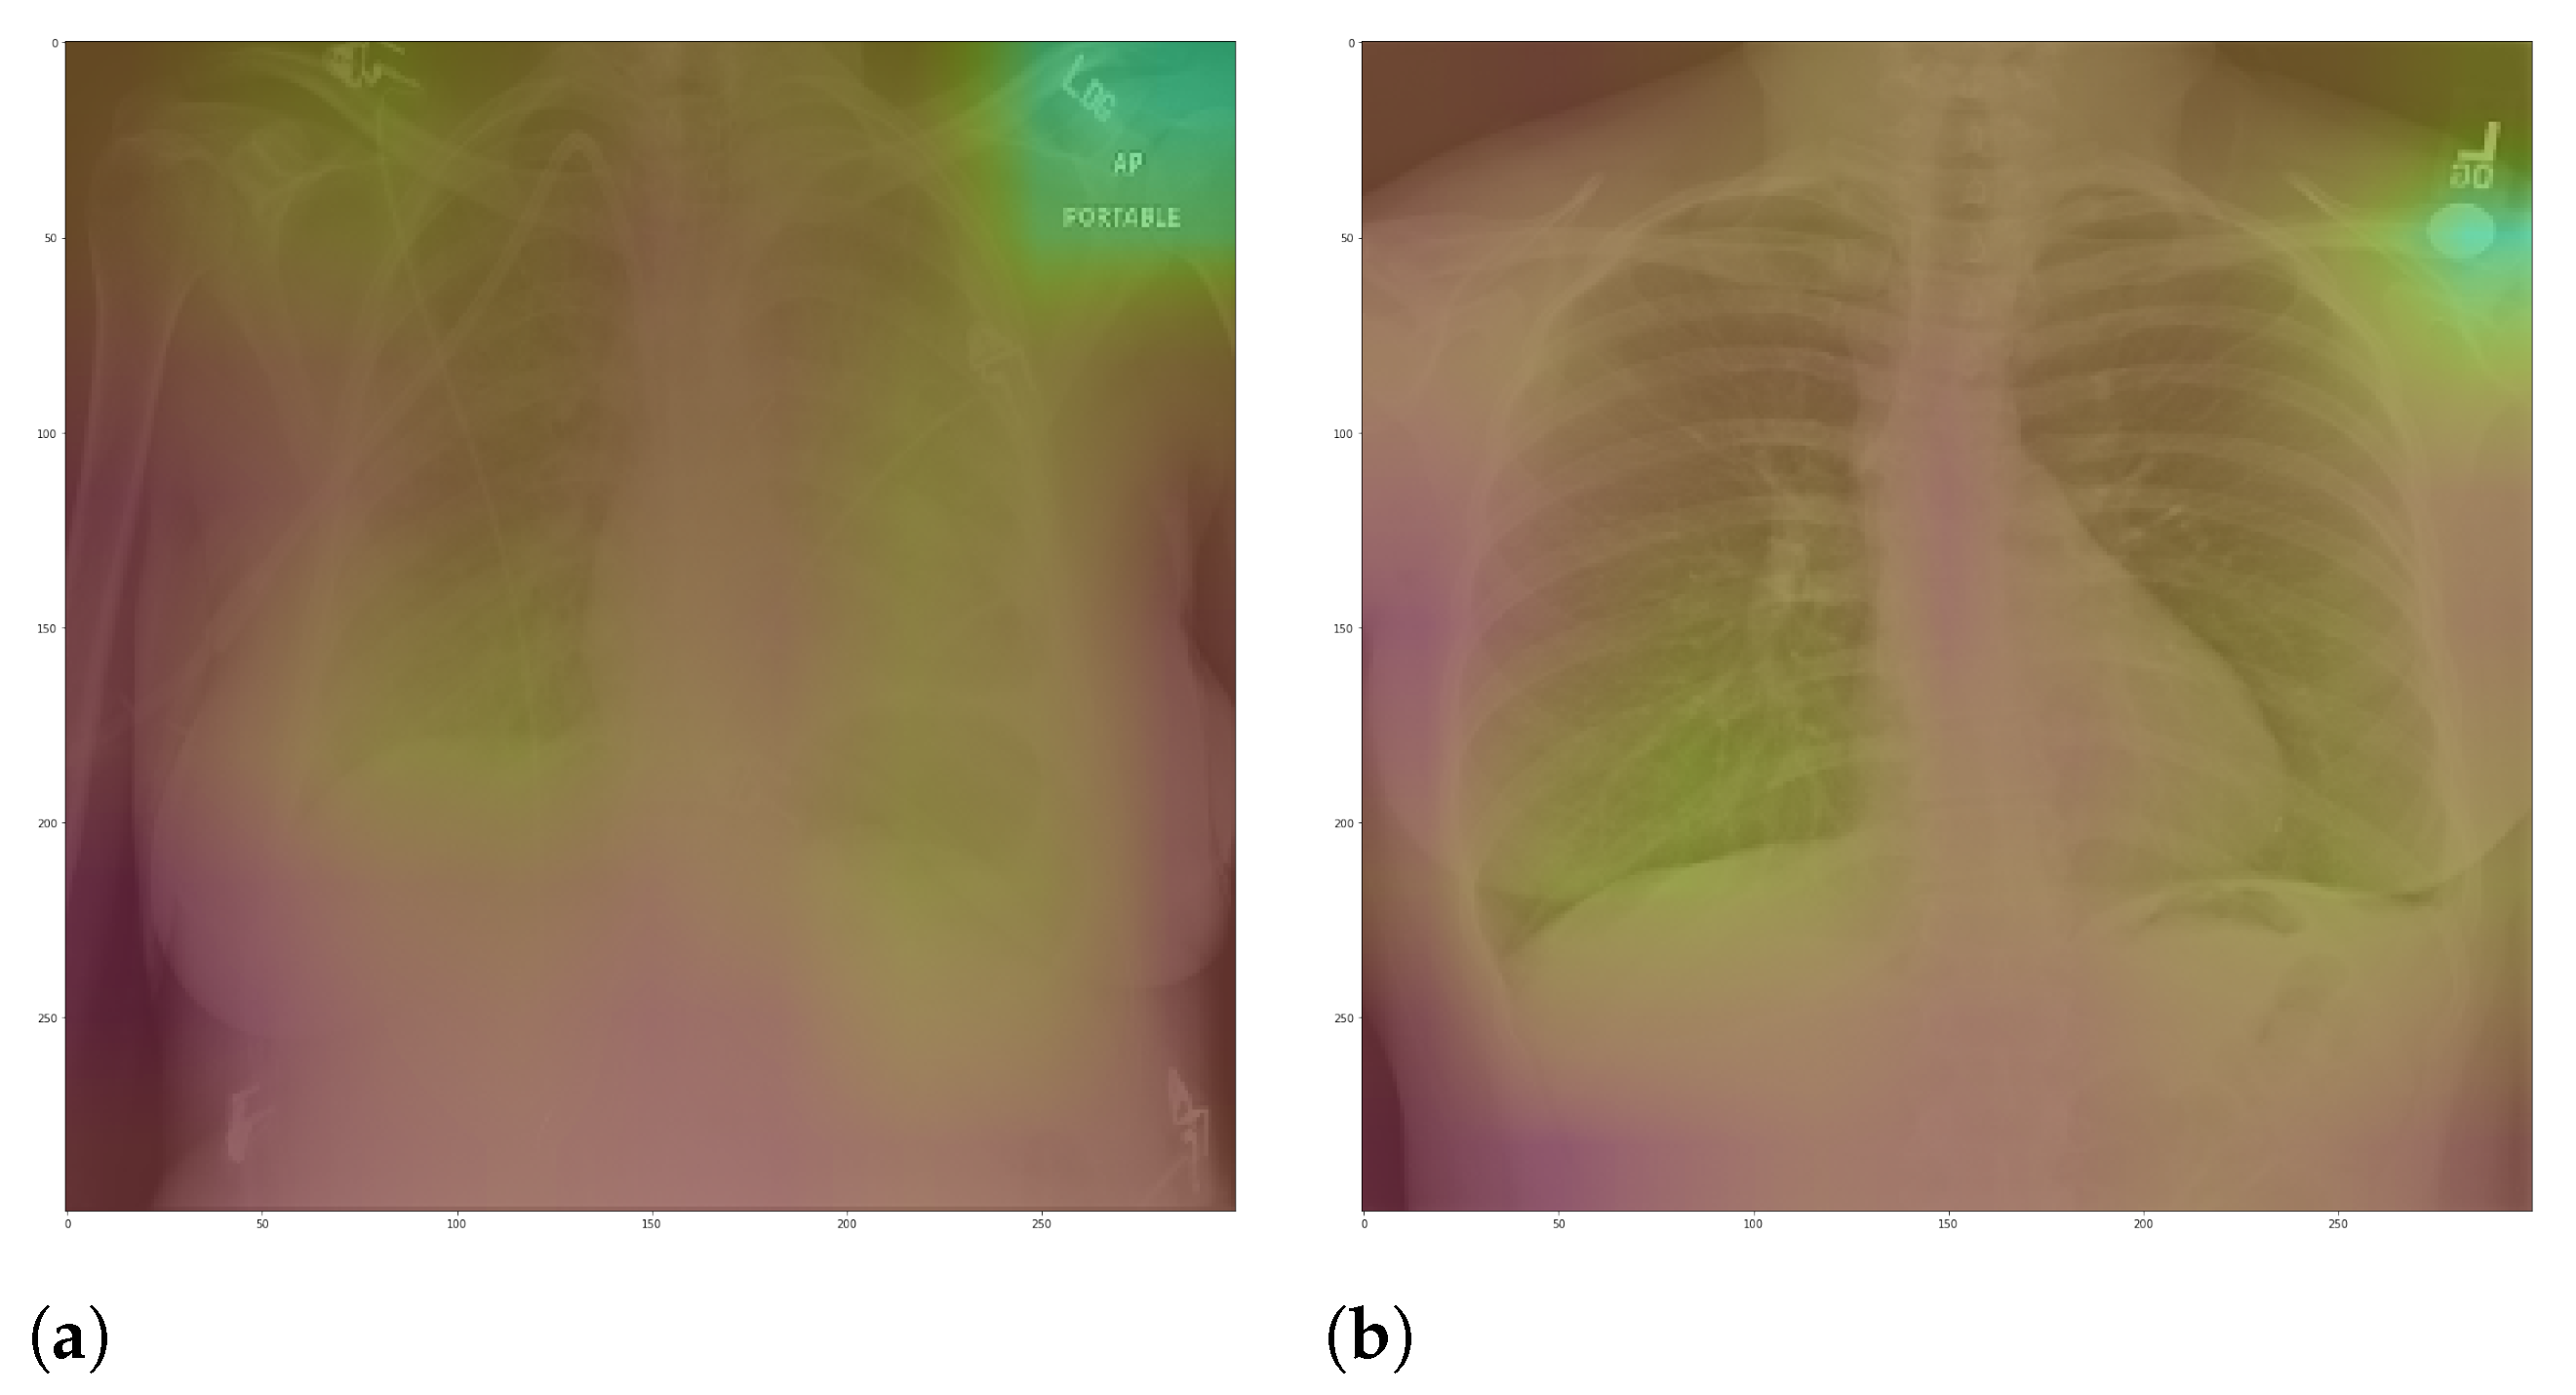

Specifically, in deep models, any extra information can lead to model overfitting. This is especially important in CXR since many images contain burned-in annotations about the machine, operator, hospital, or patient.

Figure 3 presents an example of CXR images with burned-in information.

Figure 13 presents some examples of the Grad-CAM explanation showing that the model is actively using burned-in annotations for the prediction. The LIME heatmaps presented in

The most affected class by lung segmentation is the COVID-19, followed by Lung opacity. The Normal class had a minimal impact. The best F1-Scores for COVID-19 and Lung opacity using full CXR images are 0.94 and 0.91, respectively, and after the segmentation, they are 0.83 and 0.89, respectively. We conjecture that such impact comes from the fact that many CXR images are from patients with severe clinical conditions who cannot walk or stand. Thus the medical practitioners must use a portable X-ray machine that produces images with the “AP Portable” annotation and that some models might be focusing on the burned-in annotation as a shortcut for the classification. That impact also means that the classification models had trouble identifying COVID-19.